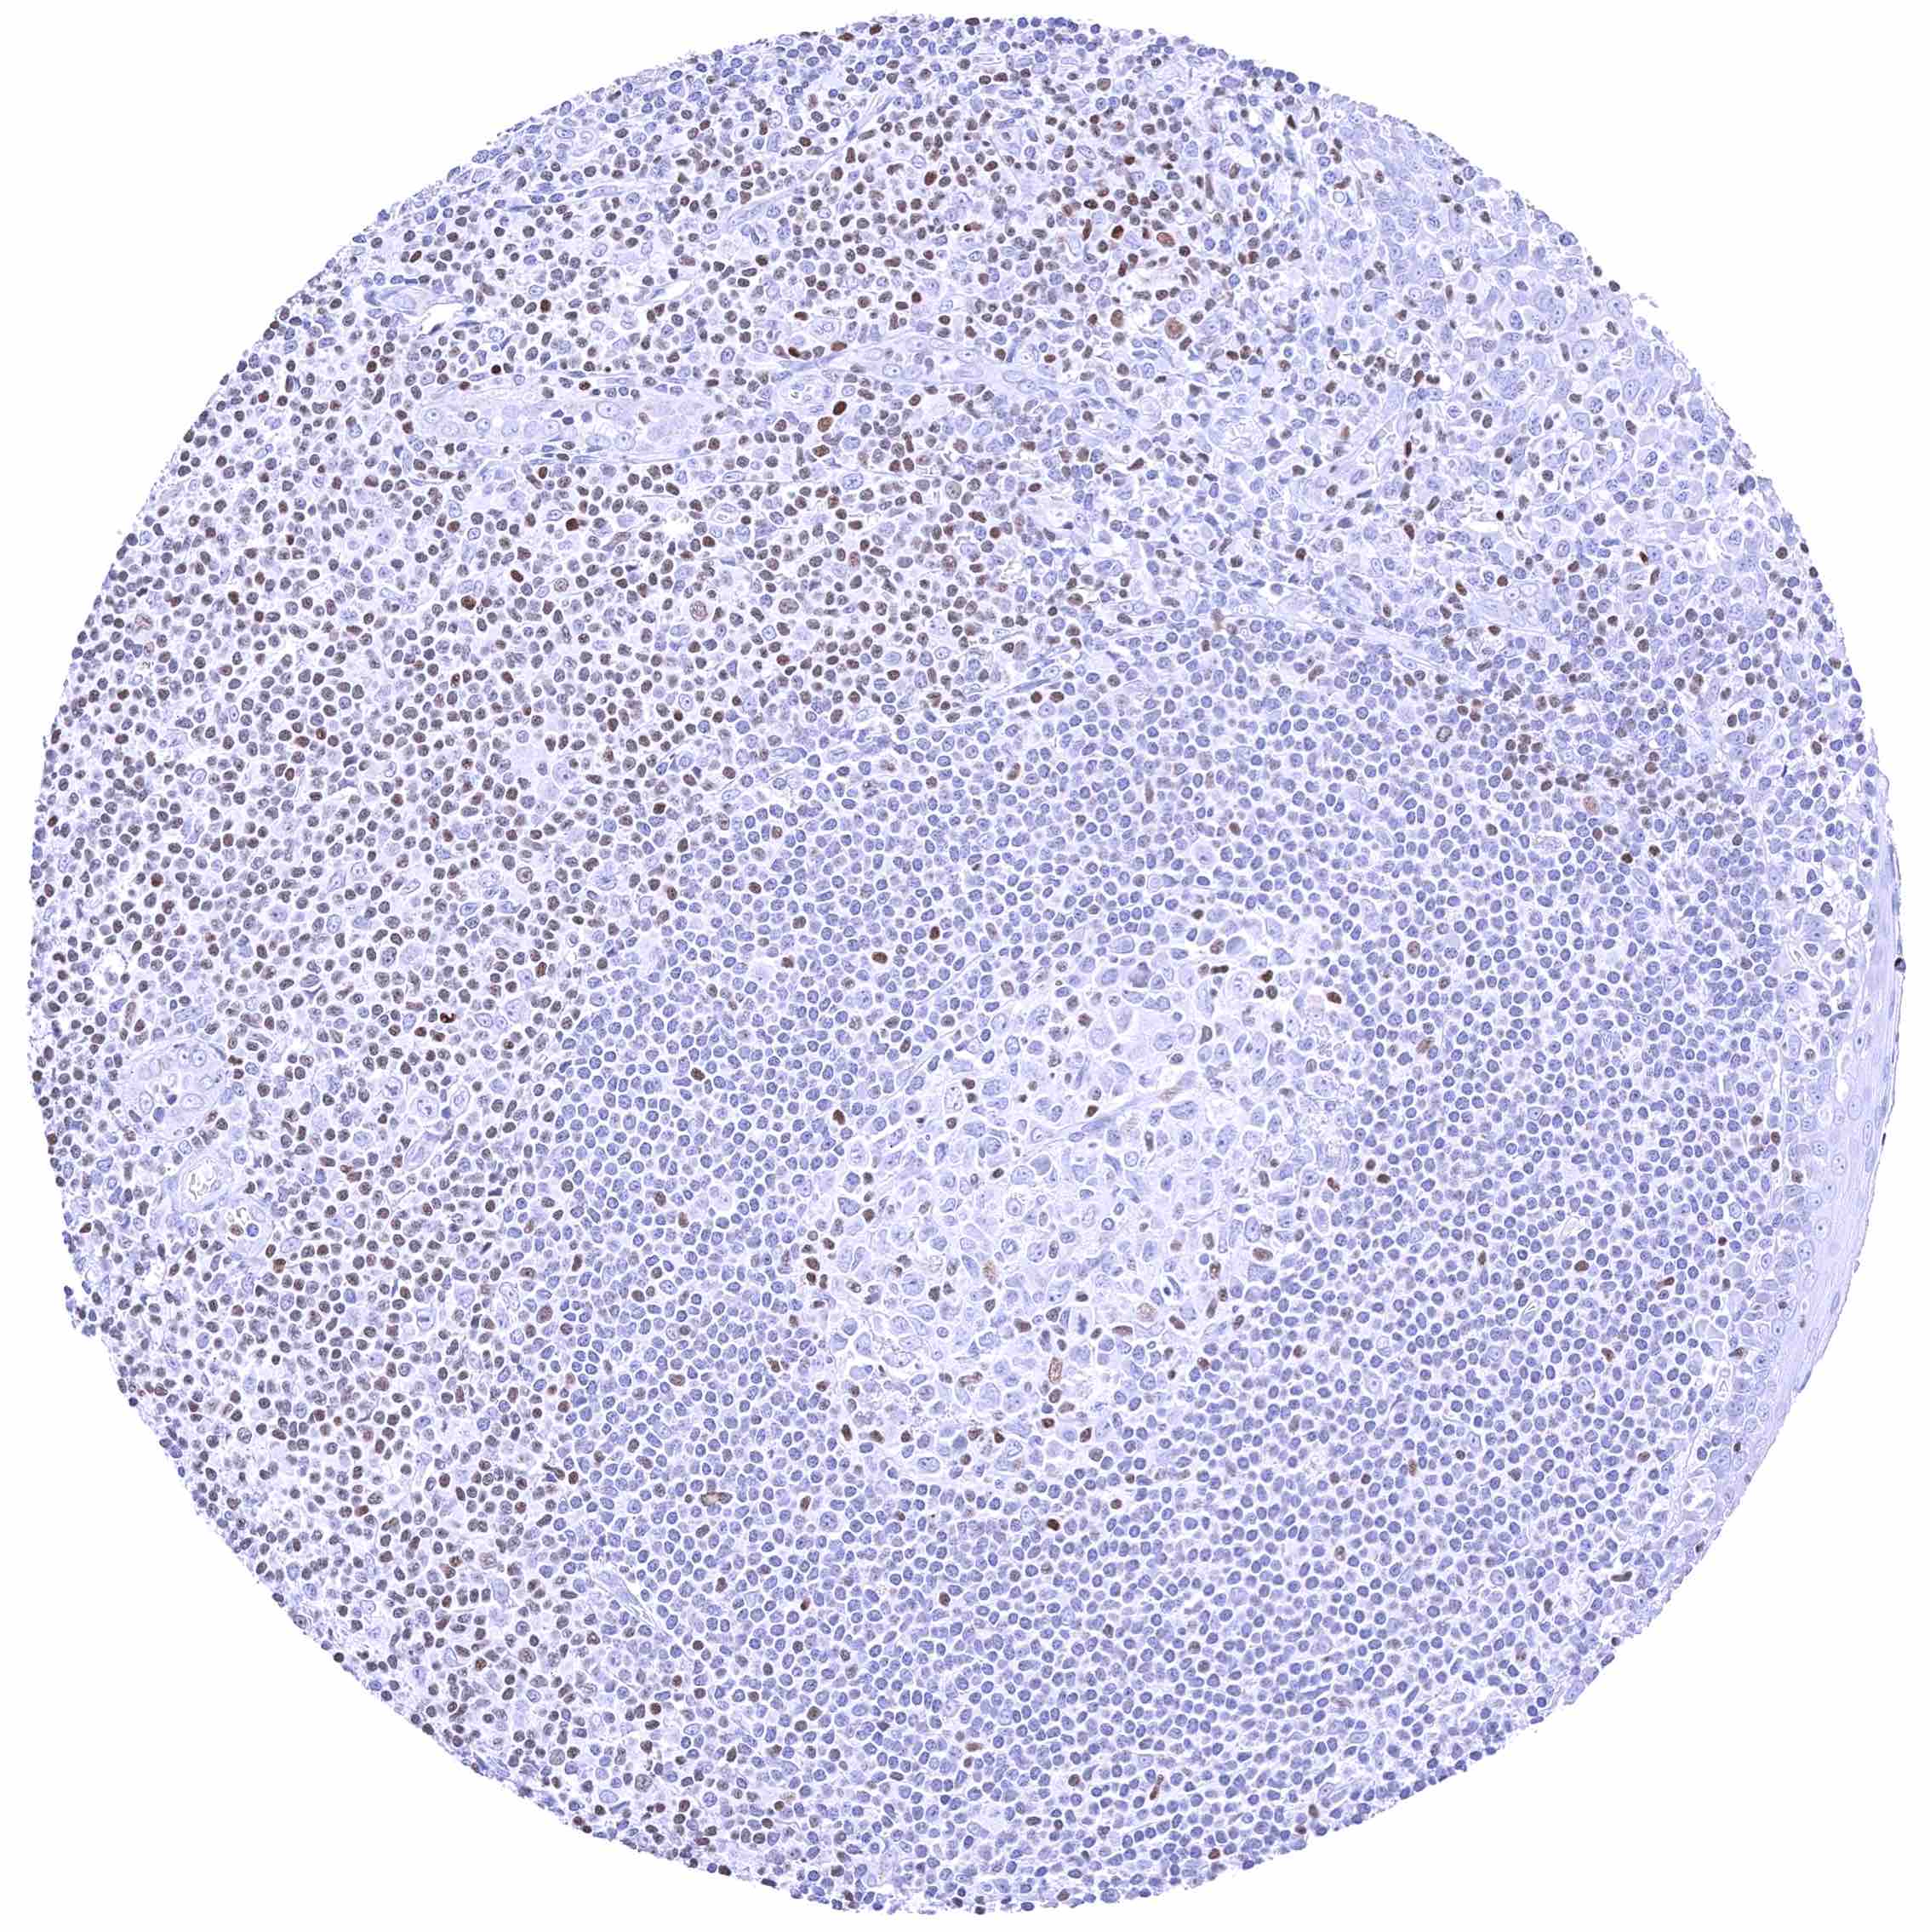

Lymph node – Nuclear GATA3 positivity of numerous lymphocytes.